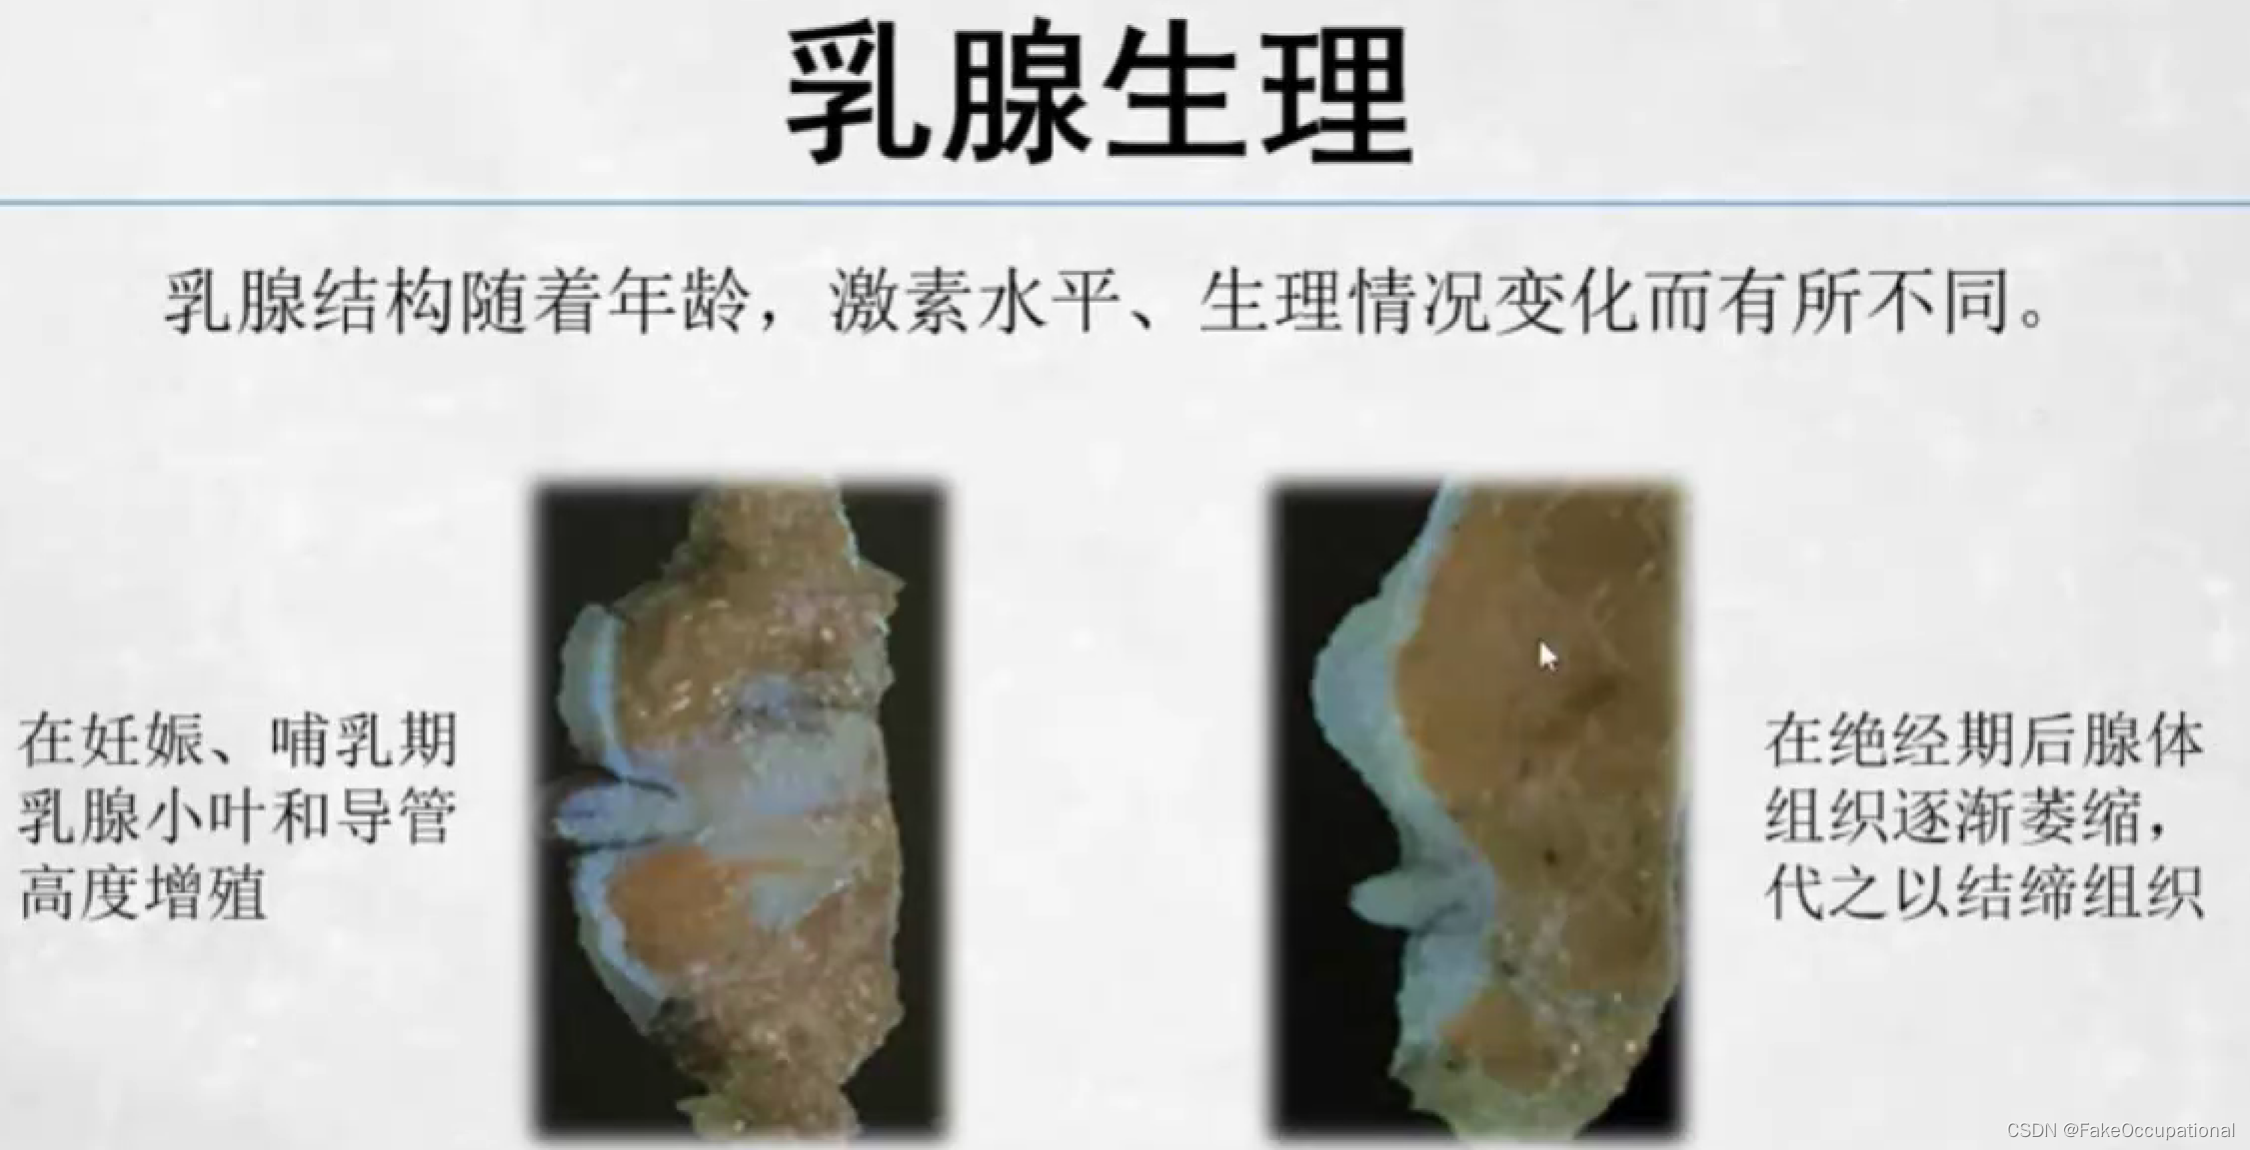

乳腺的生理解剖概要

乳腺的生理解剖概要